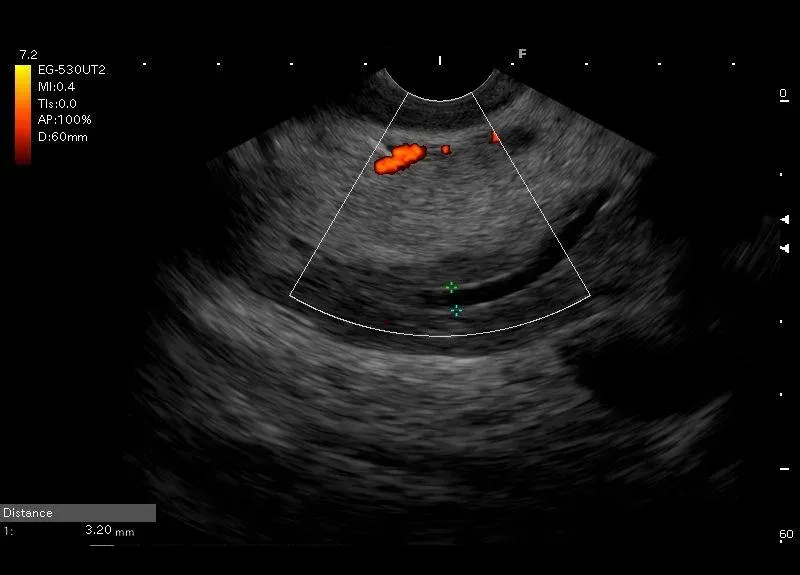

Widoczna w głowie trzustki różnica echogenicznoczności o charakterystycznym położeniu i kształcie - zawiązek brzuszny i przewód Wirunga